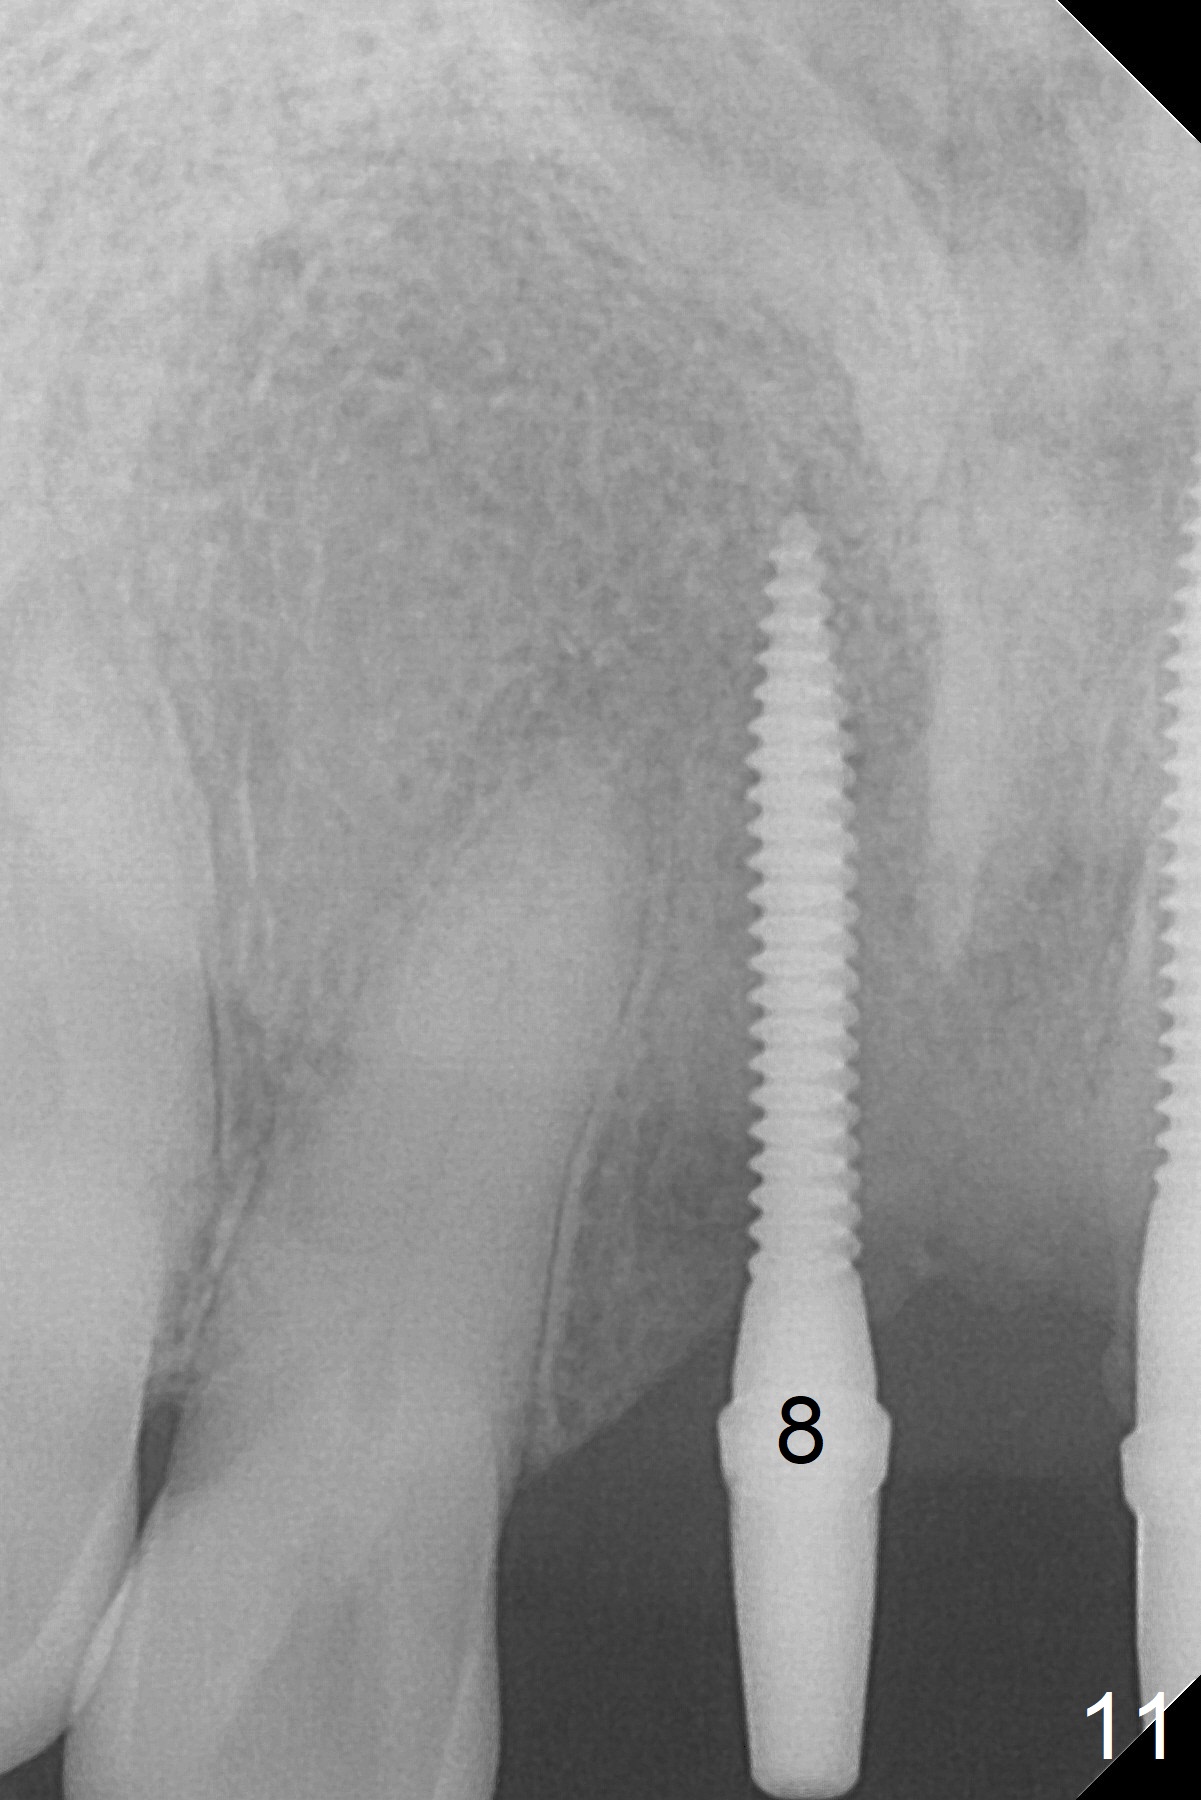

Change in trajectory at #8 seems acceptable (Fig.3 (arrowheads: upper midline suture)). But it relapses when a 2x14(2) mm implant is placed (Fig.4 (2x14(4) mm at #9)). It appears that a drastic change in trajectory is necessary (Fig.5). In fact it is difficult to change the trajectory with the flexible 1.2 mm drill. Lindamann bur can be used for this purpose initially (coronally). The osteotomy should be moved mesially prior to reuse of the 1.2 mm drill for depth (Fig.10) and re-placement of the 2x14(2) mm implant (Fig.11).